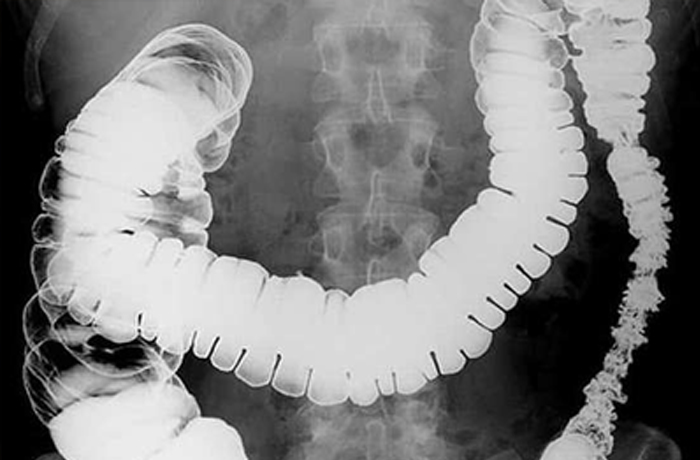

Рентгеноскопия – метод диагностики, когда при помощи рентгеновских лучей исследуется форма, размеры, положения пищевода, желудка и 12-перстной кишки. Рентгеноскопия позволяет наблюдать за состоянием и моторной функцией внутренних полых органов в реальном времени, а также выявлять их анатомические особенности и патологические изменения.

Пассаж бария по кишечнику – рентгенографическое исследование тонкого кишечника, которое выполняется для диагностики общего состояния, обнаружения патологических изменений и оценки моторно-эвакуаторной функции тонкой кишки.

Рентгеноскопия с контрастом является одним из важных методов диагностики пищевода, желудка и кишечника – без введения контрастного вещества получить изображение полых органов не представляется возможным.

Рентгенография – одномоментный снимок внутренних органов без динамики. Рентгеноскопия же позволяет отследить то, что происходит в ЖКТ в реальном времени. Аппарат делает целую серию снимков, на которой видно движение бариевой взвеси по желудочно-кишечному тракту.